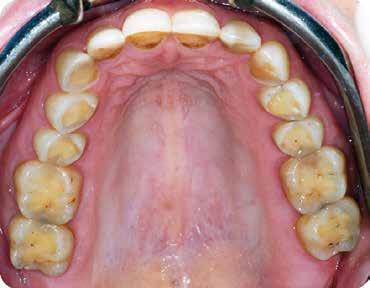

A maradó fogak gyökérreszorpciója patológiás folyamat. Az elváltozások elhelyezkedése alapján csoportosíthatjuk őket külső és belső reszorpciós folyamatokra. A külső gyökérreszorpciók egyre gyakrabban diagnosztizált formája a külső nyaki reszorpció (angolul External Cervical Resorption, ECR) [1. és 2. kép]. Az ECR egy komplex elváltozás, amely egyszerre érintheti a fog keményszöveti állományát, a parodontális szöveteket és előrehaladott esetben a pulpaszövetet is. A modern diagnosztikai eszközöknek köszönhetően egyre gyakrabban és egyre korábban kerül diagnosztizálásra ez a típusú lézió, így a kezelése is egyre inkább a mindennapi klinikum részévé válik az endodonciával foglalkozó kollégák számára. A 3 dimenziós diagnosztikai eszközök terjedésével felmerült az igény egy 3 dimenziós klasszifikációra. Patel és munkatársai 2018-ban kidolgoztak egy új klasszifikációt, amely segít az elváltozások kategorizálásában és a kezelések tervezésében [1]. A téma aktualitását jól mutatja, hogy ezzel egy időben az ESE (European Society of Endodontology) is kidolgozott egy állásfoglalást a külső nyaki reszorpciók diagnosztikájával és terápiás lehetőségeivel kapcsolatban [2].

Ötvenes éveiben járó páciensünk rutinellenőrzésre érkezett rendelőnkbe. A vizsgálat során felfigyeltünk a jobb felső metszőfogán kialakult, íny alatti elváltozásra. A röntgenfelvételen jól látható a kis méretű (Patel 1Ad) reszorpciós elváltozás [3. kép]

A megfelelő vizuális kontroll és az izolálhatóság kedvéért lebenyt alakítottunk [4. kép]. Így az abszolút izolálás már kivitelezhető volt és kofferdám izolálásban kezeltük a léziót [5. kép]. Mivel az elváltozás nem látható területen helyezkedett el, illetve a kavitás kis kiterjedését figyelembe véve kalcium-szilikát bázisú anyagot választottunk a restauráláshoz (Biodentine, Septodont) [6. kép]. Miután letelt a választott anyagunk kötési ideje (12 perc), zártuk a lebenyt [6. kép]. Páciensünk azóta is panaszmentes, kétéves kontrollon állapota rendben volt [7. és 8. kép].

Ötvenes éveiben járó hölgyet fogorvosa irányította hozzánk a bal alsó 4-es fogának nagy méretű reszorpciójával [9. kép]. A hölgy ragaszkodott foga megmentéséhez, így a kezelés megtervezéséhez CBCT felvételt készítettünk a fogról [10. kép]. A felvételen a Patel-féle klasszifikáció szerinti Patel 3Ap reszorpciós elváltozás látható. A szájüregi vizsgálat során a fog bukkális felszínén gyulladt ínyt, mély parodontális tasakot és a fog nyaki részén, a foganyagon átsejlő reszorpciós lacunát találtunk [11. kép]. A fog szenzibilitás vizsgálat során nem reagált hideg ingerlésre. A pulpális érintettség miatt elvégeztük a fog trepanálását, majd lebenyt alakítottunk a kavitás láthatóvá tételéhez [12. kép]